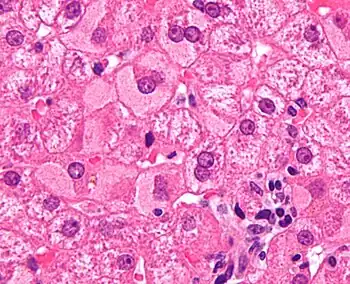

Micrograph showing ground glass hepatocytes. H&E stain.

In liver pathology, a ground glass hepatocyte, abbreviated GGH, is a liver parenchymal cell with a flat hazy and uniformly dull appearing cytoplasm on light microscopy. The cytoplasm's granular homogeneous eosinophilic staining is caused by the presence of HBsAg.

The appearance is classically associated with abundant hepatitis B antigen in the endoplasmic reticulum, but may also be drug-induced.[1][2] In the context of hepatitis B, GGHs are only seen in chronic infections, i.e. they are not seen in acute hepatitis B.